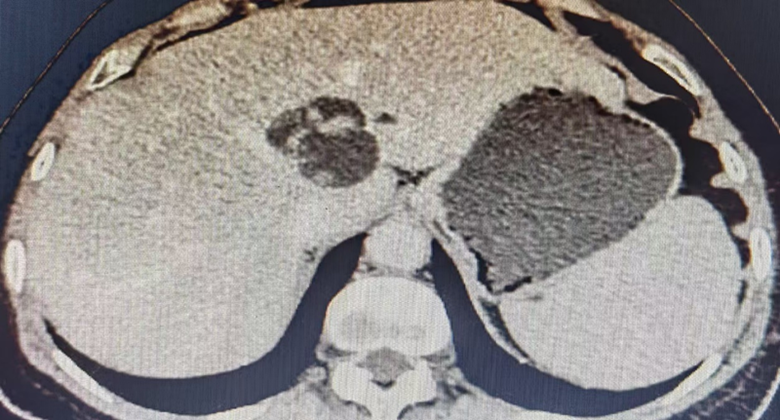

今年66岁的吴阿姨因“反复上腹胀痛半年”在我院诊断为左肝肿瘤性病变。病灶紧贴肝中静脉、肝左静脉、下腔静脉、门静脉矢状部等重要解构,手术难度大,风险高。为最大程度兼顾肿瘤根治性和患者安全,经充分术前准备后,肝胆胰外科团队联合手麻团队于9月13日上午顺利为吴阿姨行了“荧光腹腔镜解剖性左半肝联合左尾叶切除术+胆囊切除术”,用时3小时余完整切除计划区域,出血30ml,没有安置腹腔引流管。手术全程平稳顺利。在“少痛、早动、早食、安心”系列加速康复外科措施支持下,吴阿姨于手术后第3天顺利康复出院。

为什么吴阿姨在肝脏大手术后3天就能快速康复出院呢?主要有三方面原因:一是在吴泓教授、杨家印教授等多位上级医院专家教授的帮助指导下,肝胆胰外科自2016年开始推行以腹腔镜微创技术和精准解剖技术为基础的微创诊疗体系,截至目前科室微创手术率达到90%以上;二是肝胆胰外科医护团队积极推行加速康复外科理念,在患者住院期间全流程施行“少痛、早动、早食、安心”的系列加速康复外科措施;三是充分利用ICG荧光导航技术、三维重建技术、3D腹腔镜技术等先进技术助力手术质量和效率的提升。